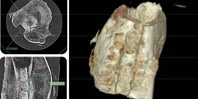

Гранулы — это каркас для формирования костной ткани, а кольцевая ДНК усиливает ее кровоснабжение и ускоряет регенерацию. Как показали исследования, средство ускоряет процесс восстановления костей. И это без использования имплантатов костной ткани пациента. Ожидается, что средство будут применять для терапии при повреждениях костей скелета, а также для наращивания костной ткани перед установкой дентальных имплантатов.

Создатели средства — компания «Гистографт» (резидент Сколково) и Институт металлургии и материаловедения РАН при поддержке Института стволовых клеток человека, Фонда Сколково и Фонда содействию развитию малых форм предприятий в научно-технической сфере. Известно, что компания также работает над несколькими материалами с факторами роста. Среди них гели, мембраны и персонализированные имплантаты, сделанные на 3D принтере.